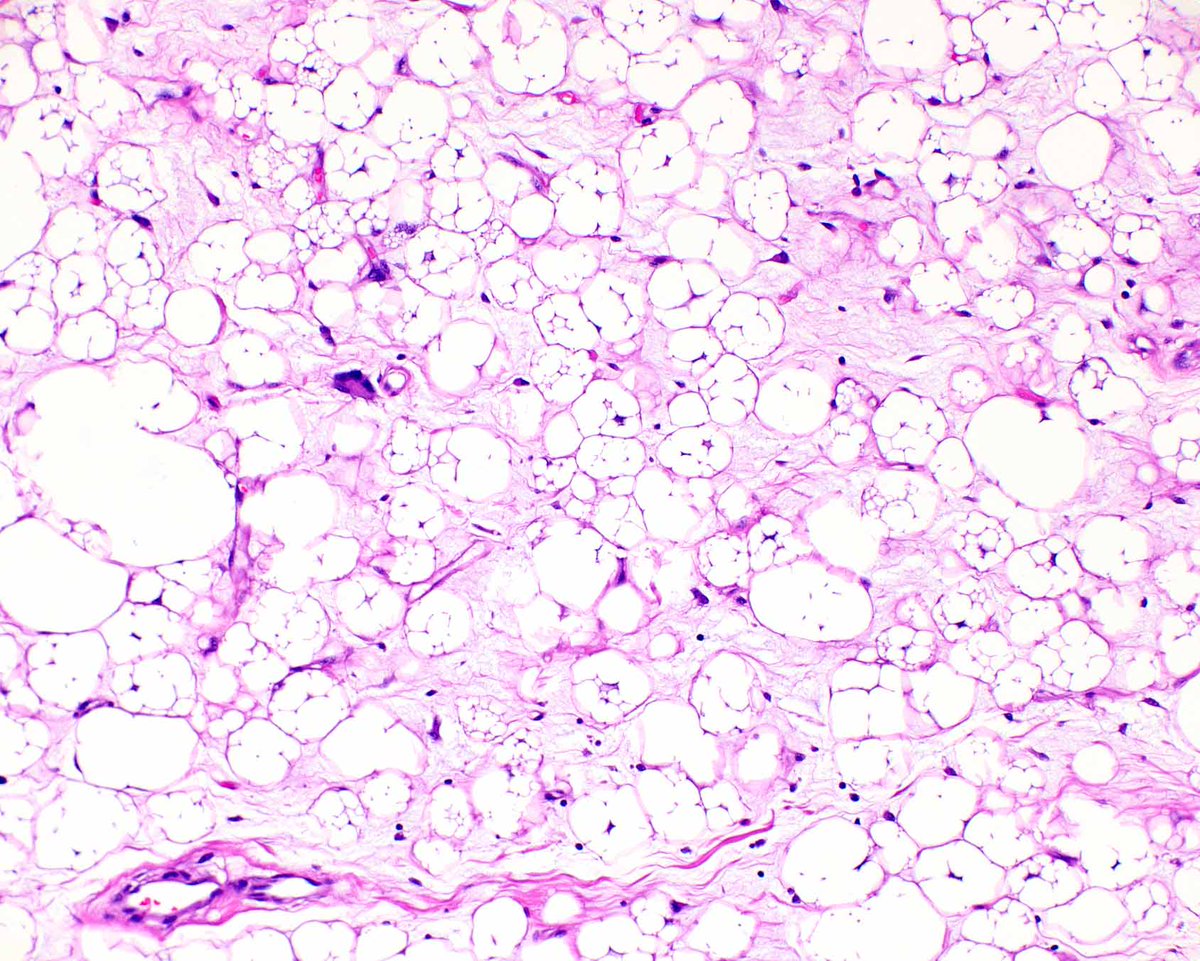

This atypical lipomatous tumor (well-differentiated liposarcoma) is unusual in containing plentiful lipoblasts.